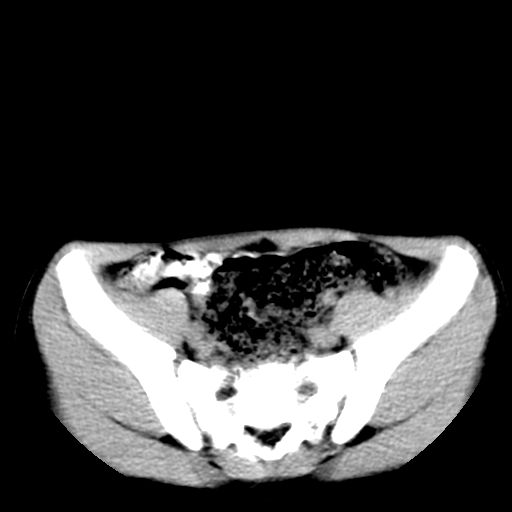

腹部好象未见异常。

腹部ct平扫未见明确异常

腹部ct平扫不能提示哪里有病变。